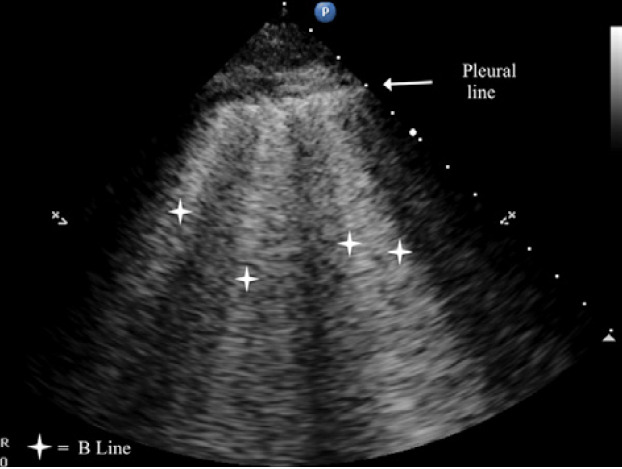

B-lines are small, well-defined comet tail-like artifacts arising perpendicularly from the pleural line (Figure 2a). During respiration, these lines move along the pleural line and may erase A-lines. One or two B-lines may be seen per intercostal space in 30% of healthy individuals, particularly in dependent regions of the lung20 B-lines indicate filling of the interstitial space and are often observed in pulmonary edema.21

The C lines are defined as hypoechoic sub-pleural focal images produced by condensed lung tissue without the presence of the visceral pleural line gap. They are typically conical or dome-shaped, thus the name cupola (Figure 2b). C lines are not true lines but are designated as such in order to maintain consistency.22

Typical patterns of ultrasound imaging are seen at various scanning points during the diagnosis of pneumonia. From the anterior perspective, typical C-lines identified by a curvilinear aspect of the pleural line are caused by adjacent consolidated tissue; as in pneumonia, the alveoli are filled with fluid (Figure 3). The non-aerated lung tissue is thus readily transverse by ultrasound beams, producing an image comparable with liver tissue.7,18